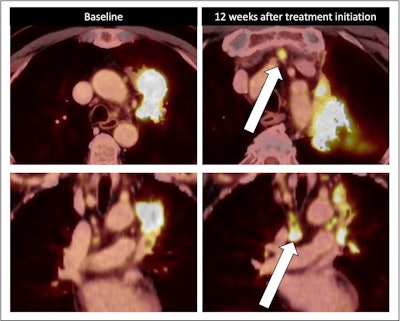

"Metabolic examinations such as [F-18] FDG-PET/CT better assess treatment response compared to morphological changes," noted Dr. Daria Kifjak; Dr. Lucian Beer, PhD; and colleagues from the Department of Biomedical Imaging and Image-Guided Therapy at Medical University of Vienna. They emphasized, however, that in addition to certain side effects, neoadjuvant chemoimmunotherapy can in rare cases induce unusual tumor reaction patterns such as a nodal immune flare, which involves immune-mediated increased lymphatic FDG uptake and/or increased lymph node size.

Nodal immune flare: 72-year-old patient with NSCLC received a neoadjuvant treatment with three cycles of ICIT + C (carboplatin/pemetrexed/pembrolizumab). 12 weeks after treatment began, the patient showed an increase in size and FDG avidity but also major pathologic response with less than 10% of vital tumor burden (ypT1a, No, Ro [local]). All figures courtesy of Dr. Daria Kifjak and Dr. Lucian Beer.